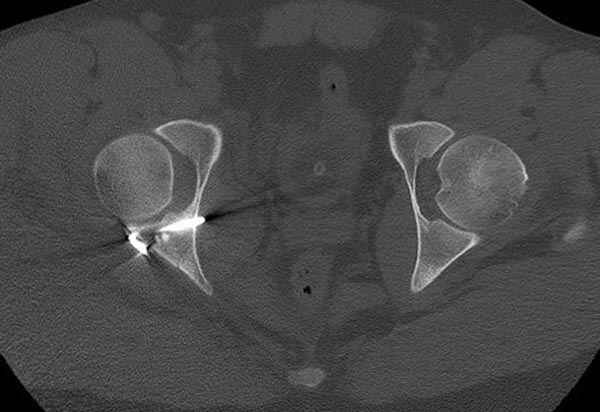

Кроме вывиха виден перелом задней стенки, насчет задней колонны не уверен (видна линия перелома дистальнее ацет. крыши - подвздошная проекция или СТ помогли бы прояснить ситуацию). Поэтому с такой ситуации только закрытое вправление без рефиксации фрагмента задней стенки может привести к рецидиву вывиха (с чем имел неприятность столкнуться не так давно).

На первый взгляд, бедро надо вправить, наложить вытяжение, и дообследовать - Judet views, CT вертлужной впадины, чтобы оценить дефект задней стенки. Вероятно, придется делать остеосинтез заднего края.

5:24 Рентгенограмма таза, вызывают врача ортопеда (снимок N1), его диагноз: закрытый переломо-вывих правого тазабедренного сустава, получает добро на закрытую репозицию в приемном отделении

5:38 Дважды неудачная попытка закрытой репозиции в приемном отделении

N 2